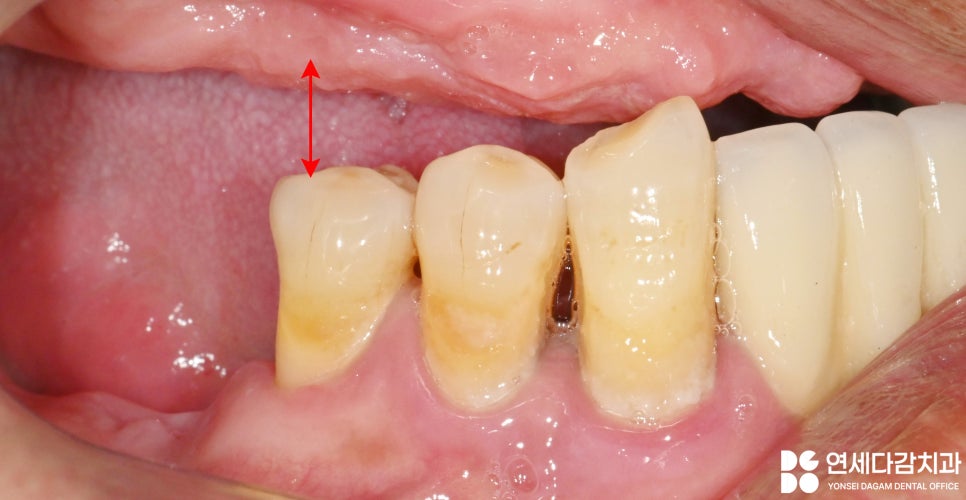

잇몸뼈가 흡수되고

의치를 오래 사용하여

닳게 되면 수직 고경이 낮아지는데요.

수직 고경이란

자연스럽게 이가 맞물렸을 때의

코끝과 턱 끝의 수직 거리를 뜻합니다.

이것은 얼굴 및 턱의 뼈 형태,

관련 근육의 길이,

위 아랫니의 교합 관계에

의해 결정됩니다.

골흡수로 인한 안모 변화,

특히 수직 고경의 감소는

입술 주변의 주름 증가를 만듭니다.

따라서 가락시장역 치과 에서는

수직 고경을 높여

회복하는 것을 목표로 하였습니다.